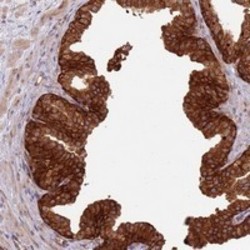

Supportive validation

- Submitted by

- Abnova Corporation (provider)

- Main image

- Experimental details

- Immunohistochemical staining of human prostate with LRRC73 polyclonal antibody (Cat # PAB24513) shows strong cytoplasmic and membranous positivity in glandular cells at 1:50-1:200 dilution.

- Validation comment

- Immunohistochemistry (Formalin/PFA-fixed paraffin-embedded sections)